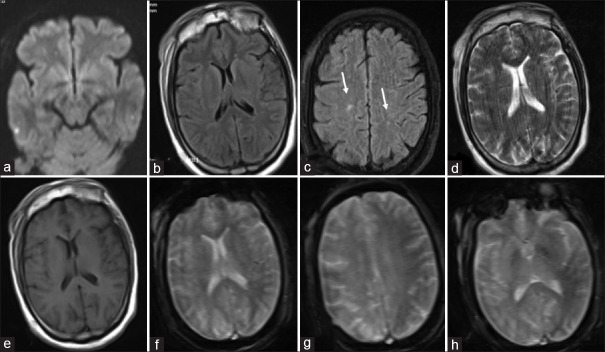

Abstract Image